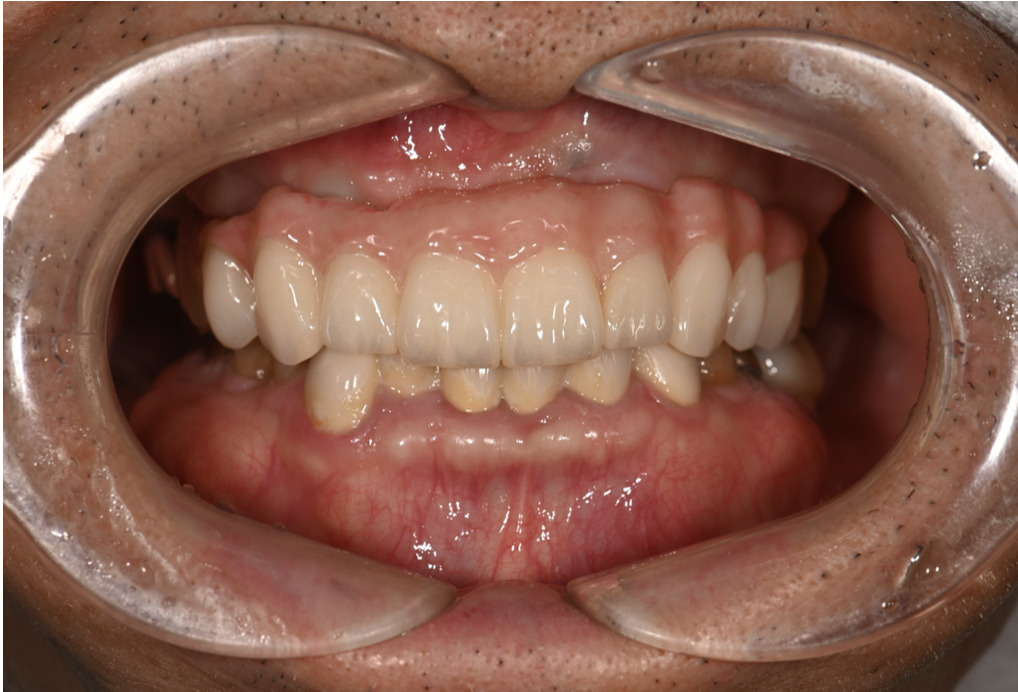

| 主訴 | 全体的にきれいにしたい |

|---|---|

| 治療内容 | 午前中に上下顎共に重度の歯周病、虫歯のため全ての歯を抜歯させていただき下顎はインプラントの土台を3本埋入し歯型を取り午後に上部構造(下顎全ての歯)を装着、上顎は一度総入れ歯を装着させていただきました。 治療が1日で完了しその日のうちに噛めるようになります。 |

| 治療期間 | 2回(1回目に資料取りをさせていただき2回目に下記の全ての治療をさせていただきました。) |

| 治療費 | 250万円 |

| 治療 リスク | 抜歯した部位などに関しては当日痛みが出ますので痛み止めなどを処方させていただきます |